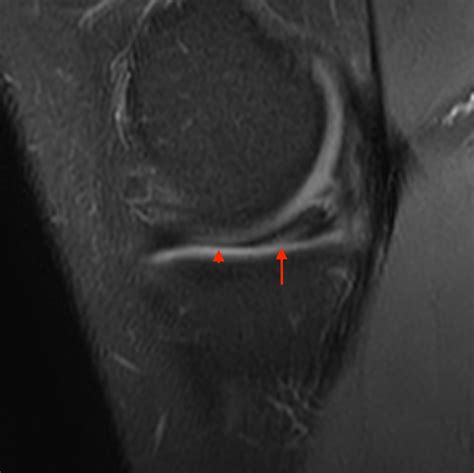

To grasp the severity of this injury, it helps to visualize the knee joint. Your meniscus is a wedge-shaped piece of fibrocartilage that sits between your thigh bone (femur) and your shin bone (tibia). It distributes weight and stabilizes the joint. When a bucket handle meniscus tear occurs, the inner portion of the cartilage detaches from the main body but remains attached at the front and back. This loose piece can then displace, or “flip,” into the center of the joint, physically blocking the knee from moving normally.

2. Imaging Tests: While X-rays are useful to rule out bone fractures, they cannot visualize the meniscus. An MRI (Magnetic Resonance Imaging) scan is the gold standard for diagnosing a bucket handle meniscus tear, as it provides detailed images of the soft tissue cartilage.